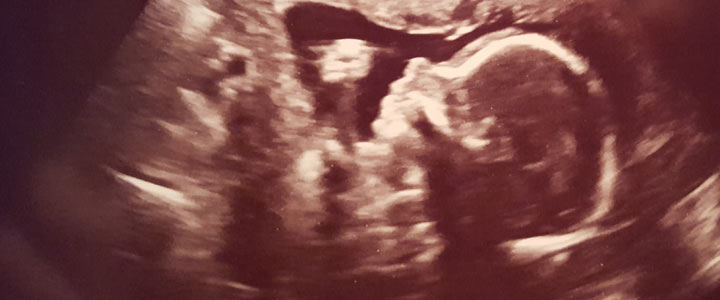

Na het bekijken van mijn eierstok draaide hij het echoapparaat naar mijn baarmoeder. Hier was een kleine zwarte cirkel te zien waarin een klein garnaalachtig vormpje dreef. De arts vertelde ons dat het hartje al klopte en dit een goed teken was. Middenin dat inimini garnaaltje knipperde een stipje, aan, uit, aan, uit. Voor de zoveelste keer in de afgelopen maanden rolde er tranen over mijn wangen. De arts vertelde dat alles er goed uit zag en dat er geen reden meer was voor mij om naar het ziekenhuis te komen; ik mocht naar een verloskundige toe! Op de terugweg in de auto besloten mijn vriend en ik om ons garnaaltje Frummelke te noemen. (Zo werd ons kindje door iedereen genoemd totdat we een echte naam hadden uitgekozen.)

Verder mat ze mijn bloeddruk en werd ik gewogen. Toen was het tijd voor de eerste echo bij de verloskundige. Het garnaaltje had armpjes, beentjes en een duidelijk hoofdje gekregen. Waar mijn moederhart werd overladen door liefde was op het moment dat onze Frummelke begon te wiegen in mijn baarmoeder. Het was prachtig om te zien dat ons kleine wondertje zich bewoog als een klein mensje.